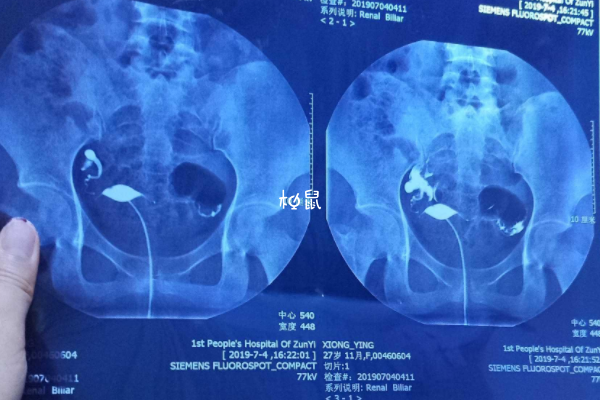

输卵管造影经X线的子宫输卵管造影是通过导管向宫腔及输卵管注入造影剂,利用X线诊断仪行X线透视及摄片,根据造影剂在输卵管及盆腔内的显影情况来了解输卵管是否通畅、阻塞部位及宫腔形态的一种检查方法,很多人听说它是一项手术都认为其过程很麻烦,但其实输卵管造影流程还是很简单的。

输卵管造影是临床上应用较为广泛的方法之一。经X线的子宫输卵管造影是通过导管向宫腔及输卵管注入造影剂,利用X线诊断仪行X线透视及摄片,根据造影剂在输卵管及盆腔内的显影情况来了解输卵管是否通畅、阻塞部位及宫腔形态的一种检查方法,操作方法也比较简单。